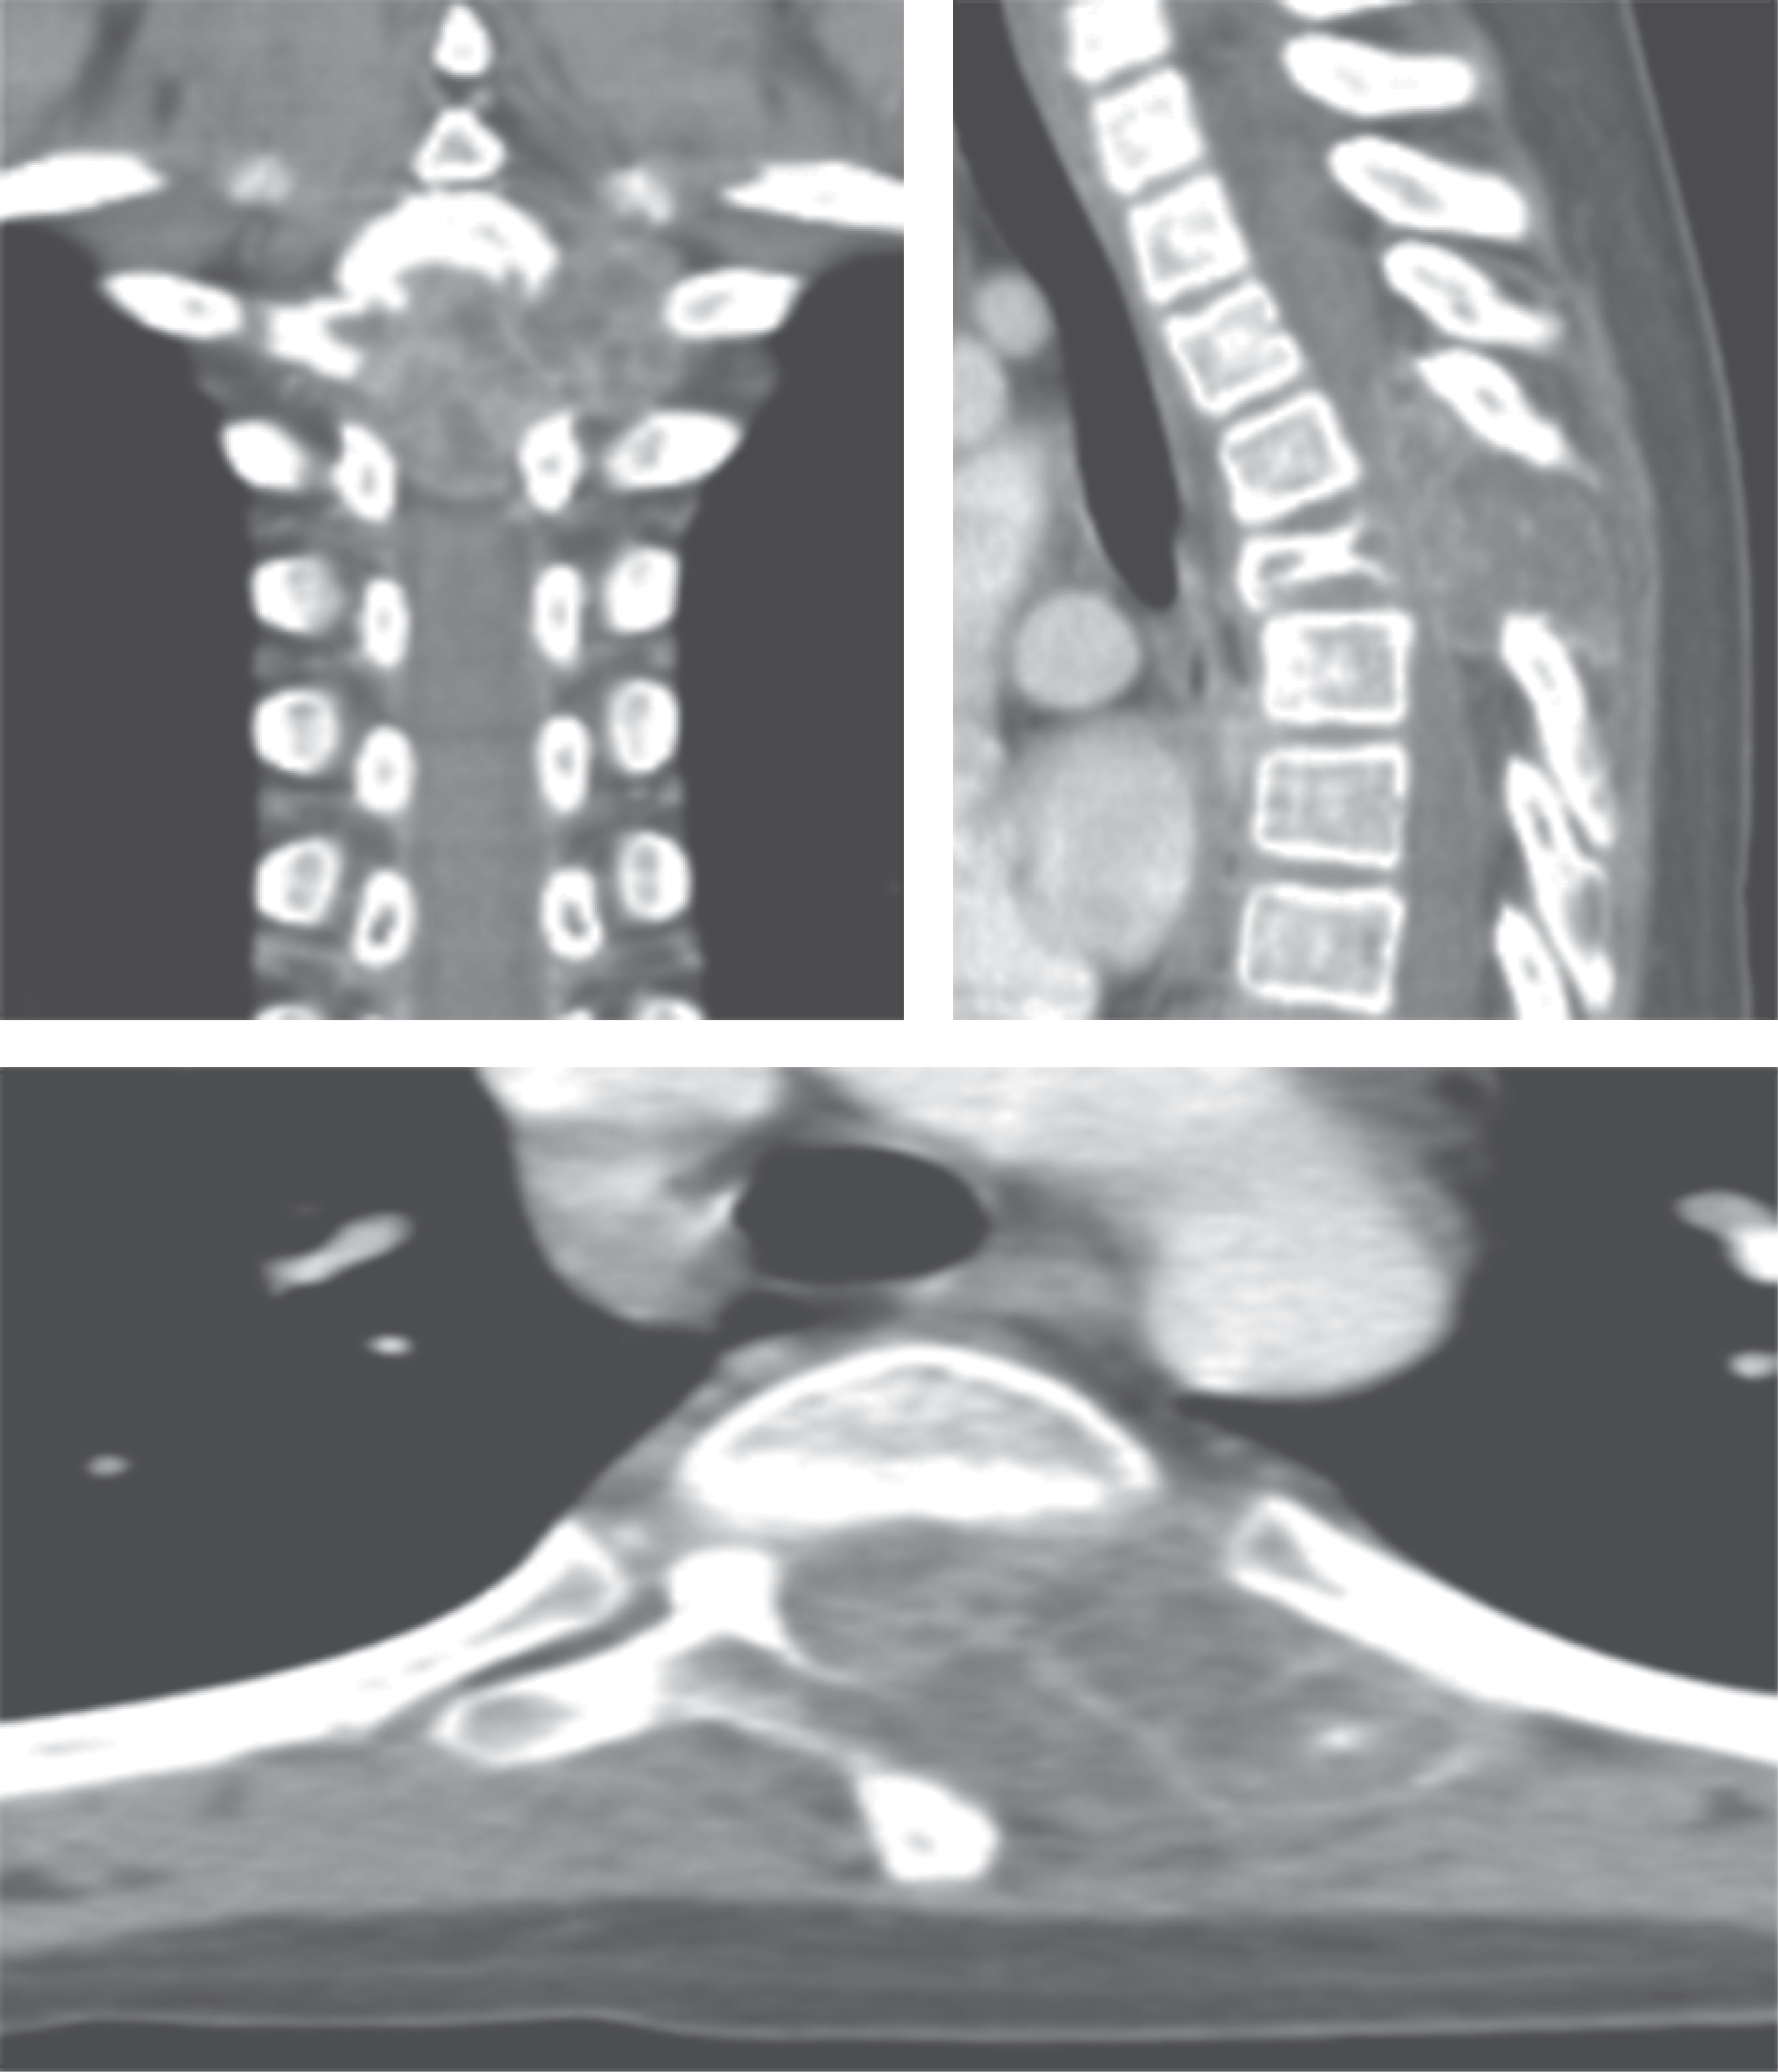

Paciente masculino de nueve años, sin antecedentes heredofamiliares relevantes o presencia de comorbilidades previas, inicia con dolor a nivel dorsal, el cual es tratado conservadoramente, remitiendo de forma parcial; posteriormente presenta alteraciones de la marcha, por lo que acude a su hospital general de zona donde se le integra el diagnóstico de cerebelitis y se establece manejo conservador, con mejoría parcial. Es valorado por el Servicio de Neurocirugía Pediátrica en el Hospital Centro Medico "La Raza" por persistencia de alteraciones en la marcha, a la cual se agrega paraparesia progresiva y dolor torácico, integrándose diagnóstico de probable síndrome de Guillain-Barré, por lo que se le solicita resonancia magnética y tomografía, donde se aprecia a nivel de T4 tumoración con crecimiento intrarraquídeo extradural que condiciona compresión de 50% del canal medular (Figura 1). Se realiza biopsia y resección intralesional del tumor, con resultado de esta biopsia de tumor de células gigantes con componente de quiste óseo aneurismático y es egresado a su domicilio (Figura 2). Sin embargo, el paciente es reingresado al servicio de neurocirugía pediátrica por persistencia de paraparesia, por lo que se decide realizar nueva resonancia magnética en la que se observa colapso vertebral, cifosis segmentaria, por lo que es enviado al Hospital de Traumatología y Ortopedia de Lomas Verdes.

Evaluación de estudios de imagen: en la tomografía realizada inicialmente se observa en corte sagital pérdida de la curvatura normal de la columna con presencia de colapso vertebral a nivel de T4 con lesión tumoral de patrón geográfico (Figura 1), lobulada, que compromete apófisis espinosa. En el corte axial se observa compromiso del cuerpo vertebral, pedículo, lámina y unión costovertebral izquierda con invasión al conducto medular, lo cual explicaría la paresia de miembros inferiores y alteraciones de la marcha que presentaba el paciente.